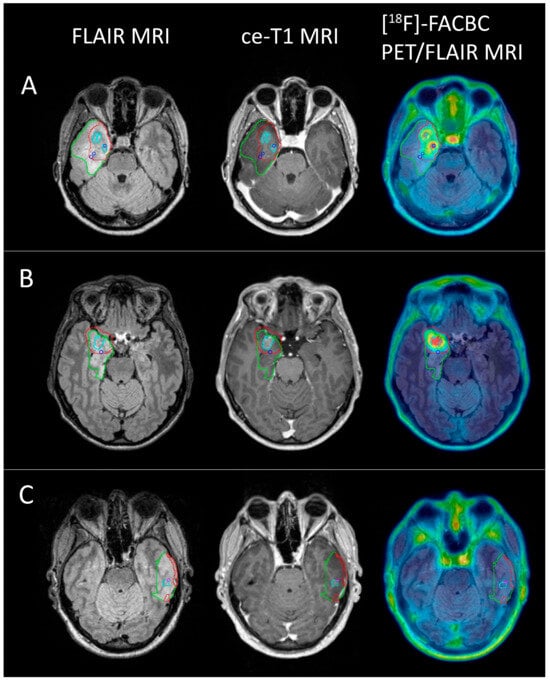

In total, 19 biopsies were sampled from the eight patients with glioblastoma, of which 16 were classified as tumor tissue and 3 as non-tumor tissue. With a TBR threshold of 2, the PET volume included 14 of the tumor-positive biopsies (87.5%), while the ce-T1 volumes included 5 (31.3%). Of the three biopsies classified as non-tumor tissue, one fell within the PET volume, while two fell within the ce-T1 volumes. Examples of PET volumes and MRI volumes for three of the patients are shown in Figure 6.

Figure 6. FLAIR (green), PET (red), and ce-T1 (cyan) MRI volumes for 3 glioblastoma patients ((A) female, 52; (B) male, 46; (C) female, 50) shown on FLAIR MRI, ce-T1 MRI, and PET/FLAIR images. Blue circles show biopsy coordinates classified as HGG (A,B), while the pink circle shows biopsy coordinates classified as non-tumor tissue (C). Two HGG biopsies from (A) and one from (B) did not show contrast enhancement, but were positive for [18F]-FACBC PET at a threshold of TBR = 2. One non-tumor biopsy from C was ce-T1 positive, but did not have [18F]-FACBC uptake.